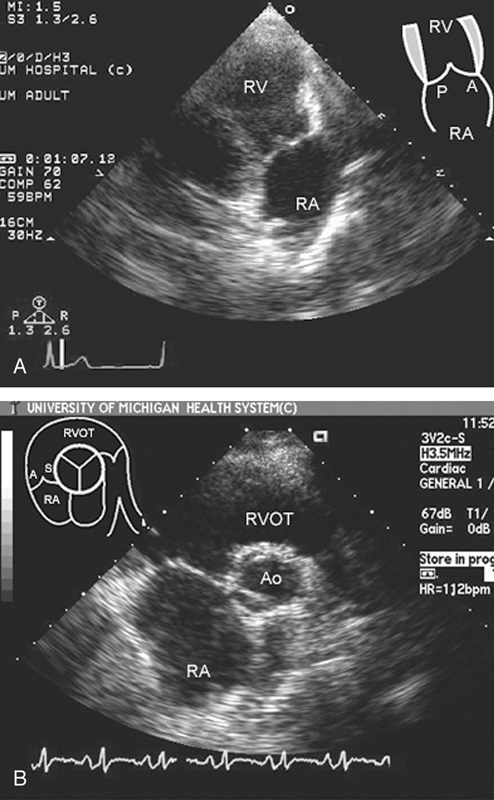

فحوصات تشخيصية لبعض امراض القلب والشرايين التاجية